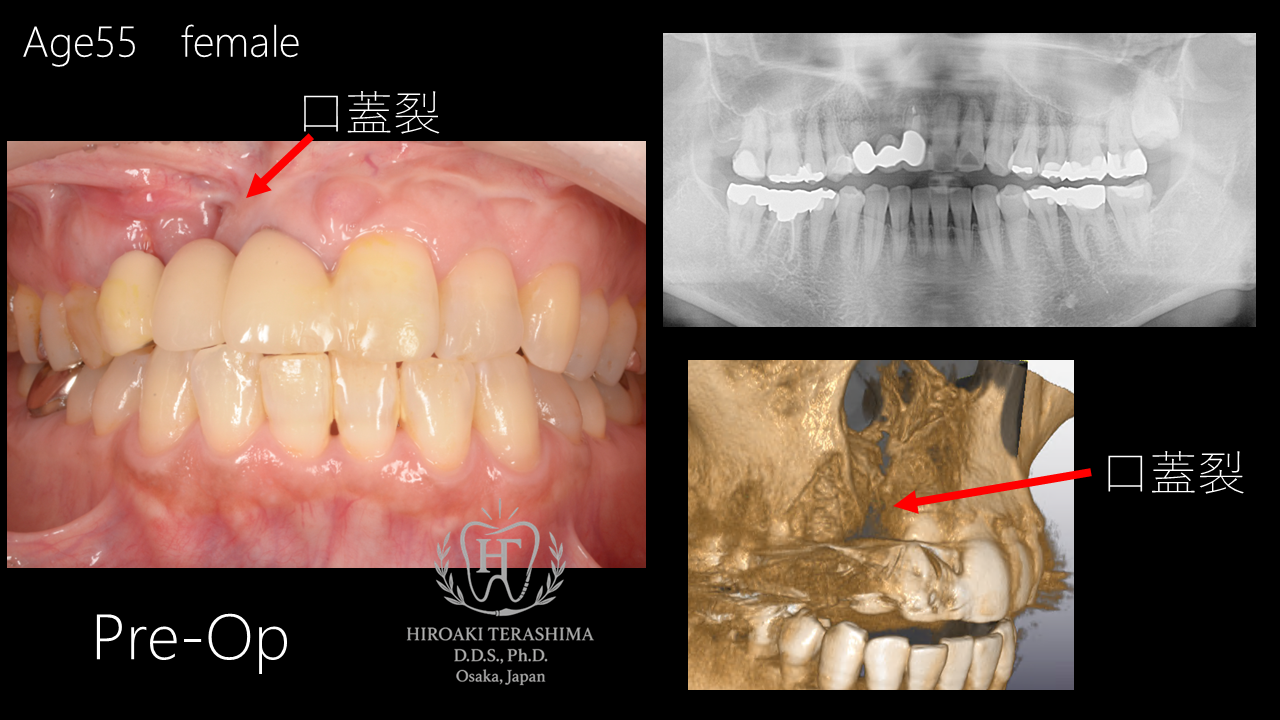

2026/02/06前歯のインプラント治療と矯正治療を併用した症例~口蓋裂患者様~

― 抜歯即時インプラント埋入・GBR・歯肉移植(CTG)・マウスピース矯正 ―

術前診断(Pre-Op)

55歳女性の患者さんです。

前歯部のブリッジが脱離し、精査の結果、歯根破折を認めました。保存は困難と判断し、抜歯を伴う治療が必要な状態でした。

CT検査では、骨欠損(口蓋裂)を認めました。